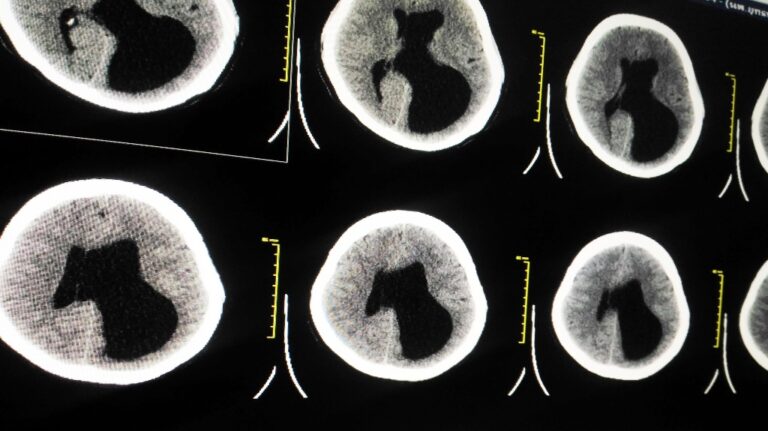

When a baby is diagnosed with Hypoxic Ischemic Encephalopathy, it can turn what should be a joyful experience into something incredibly difficult. Suddenly, instead of planning for first steps and baby milestones, parents are facing tough medical decisions, long-term care needs, and an overwhelming mix of emotions. The impact on the entire family can be…